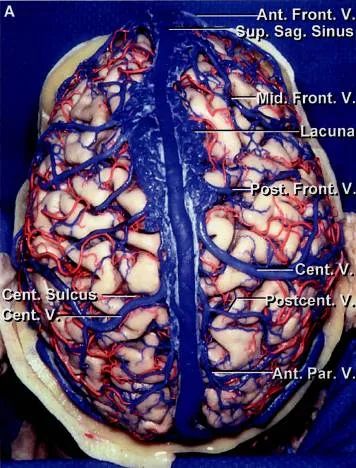

上矢状窦位于大脑镰凸缘附着处,前从鸡冠开始,沿颅内面的矢状沟向后行,至近枕内隆凸处,多偏向右移行为右横窦,也有的后端分叉,分别移行于左、右横窦(详后窦汇)。

上矢状窦的横切面呈三角形,由前向后逐渐增大。左右侧壁有大脑上静脉的开口,还有突入的蛛网膜颗粒。每侧还有三个静脉陷窝,是窦壁较薄的扩大部分。顶静脉陷窝最大,枕静脉陷窝次之,在前的额静脉陷窝最小。有作者记录:儿童静脉陷窝不明显,成年人的静脉陷窝发育良好;到老年,这些静脉陷窝有彼此连续的倾向,每侧几乎成一个长形的陷窝。静脉陷窝接受大脑上静脉的开口,每个静脉陷窝可接受1~3个静脉。静脉陷窝内有许多纤维横过,还有许多柱状、中隔状或弓形的蛛网膜颗粒从下突入至陷窝内。窦的下角也有许多横行纤维束横过。

上矢状窦接受大脑半球浅层的血液,在后端还接受经顶孔导入颅骨骨膜的静脉,静脉陷窝处导入板障静脉和硬脑膜静脉的血液。上矢状窦起始部与鼻静脉有吻合,在儿童较明显。